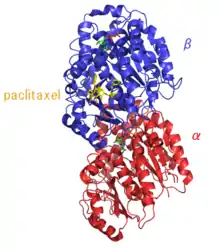

Paclitaxel is one of several cytoskeletal drugs that target tubulin. Paclitaxel-treated cells have defects in mitotic spindle assembly, chromosome segregation, and cell division. Unlike other tubulin-targeting drugs, such as colchicine, that inhibit microtubule assembly, paclitaxel stabilizes the microtubule polymer and protects it from disassembly. Chromosomes are thus unable to achieve a metaphase spindle configuration. This blocks the progression of mitosis and prolonged activation of the mitotic checkpoint triggers apoptosis or reversion to the G0-phase of the cell cycle without cell division.[23][24]

The ability of paclitaxel to inhibit spindle function is generally attributed to its suppression of microtubule dynamics,[25] but other studies have demonstrated that suppression of dynamics occurs at concentrations lower than those needed to block mitosis. At the higher therapeutic concentrations, paclitaxel appears to suppress microtubule detachment from centrosomes, a process normally activated during mitosis.[26] Paclitaxel binds to the beta-tubulin subunits of microtubules.[27]